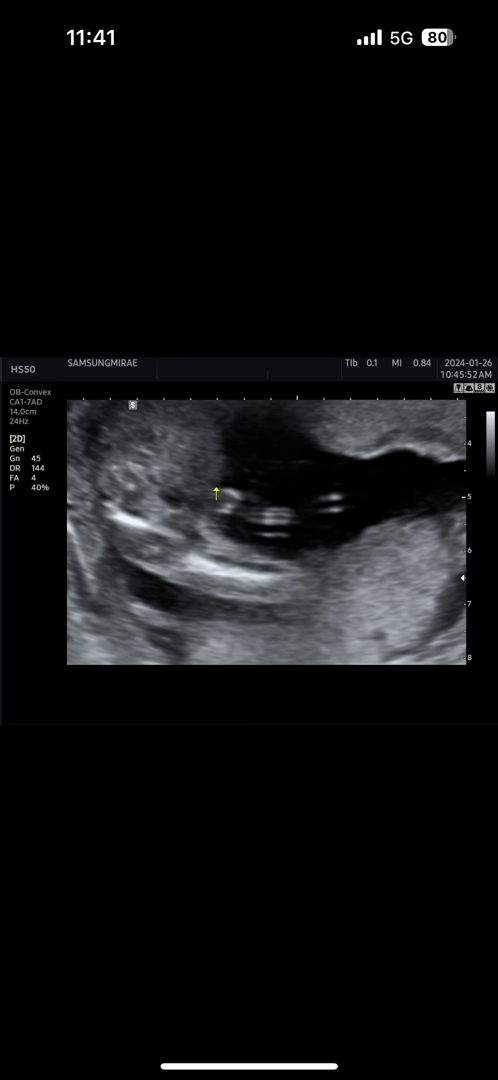

저는 배초음파로 볼때 딸인거같은데 원장님이 애매하니까 질 초음파로 다시한번 봐주셨어요 훨씬 선명하게 매끈하게 보이더라고요

탯줄때문에 애매하대용 ㅠ

탯줄이랑 같이 있어서 애매하대용 ㅠ 아들80프로라는데 반전 없을까용??

저희 아가도 초음파로 비슷하게 보엿엇어요! 그래서 의사쌤이 아들인거같긴한데 탯줄때문에 애매하다고해서 2주뒤에 다시봣는데 반전은 없더라구요 ㅎㅎㅎㅎ